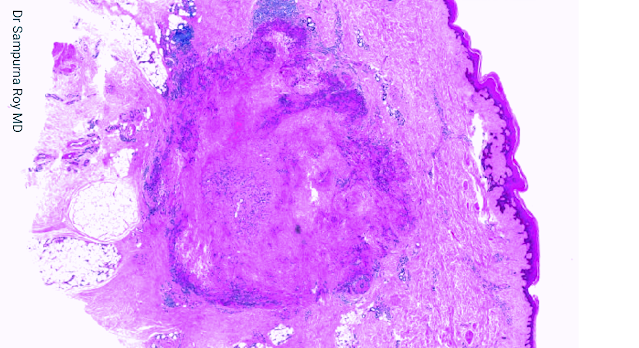

Dermatopathology Case 190

A 27-year-old man was referred to the dermatology department with a

3-month history of a rapidly growing painful mass on his right forearm

which subsequently ulcerated.